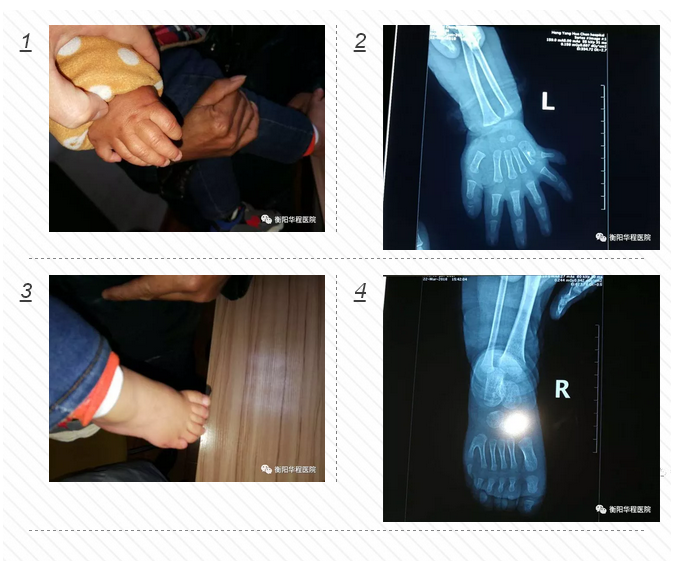

正常人一般只有兩個(gè)大拇指,可家住衡陽縣集兵鎮(zhèn)的1歲大的城城,雙手和雙腳比常人各多出1個(gè)小手指和1個(gè)小腳趾,不過在衡陽華程醫(yī)院骨科中心醫(yī)護(hù)人員的幫助下,3月23日下午,多出來的手指和腳趾已被成功切除。

面對(duì)這位只有1歲的小患者,骨科中心醫(yī)護(hù)人員進(jìn)行了一番細(xì)致檢查。尹治華醫(yī)生發(fā)現(xiàn)小城城的“多指”情況并不是特別復(fù)雜,突出的關(guān)節(jié)部位并沒有長(zhǎng)出骨頭,只需切除多出的指頭,再將表皮重新縫合,扎死血管和神經(jīng)就可以了。“孩子太過幼小,血管和神經(jīng)均很纖細(xì),需借助顯微成像技術(shù)完成手術(shù)。而留下的疤痕組織也會(huì)在成長(zhǎng)過程中逐漸減淡。”骨科中心尹治華醫(yī)生表示。3月23日小城城在全麻下行雙側(cè)多指、多趾切除功能重建術(shù),經(jīng)過一個(gè)小多小時(shí)的焦急等待,孩子平安從手術(shù)室里出來了,手術(shù)非常成功,小城城媽媽那顆懸著的心終于著了地。